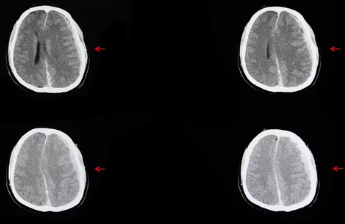

뇌출혈은 뇌 내부의 혈관이 파열되어 혈액이 뇌 조직으로 유출되는 상태를 말합니다. 이는 뇌 기능에 심각한 영향을 미칠 수 있는 의료적 긴급 상황입니다. 뇌출혈의 증상은 다양하며, 초기에는 경미할 수 있지만, 상태가 악화될 경우 생명을 위협할 수 있습니다.

뇌출혈의 초기 증상으로는 갑작스러운 심한 두통, 어지럼증, 구토, 의식 저하, 한쪽 팔다리의 힘이 빠지거나 마비되는 증상, 언어 및 발음 장애, 시각 장애 등이 있습니다. 특히, 한쪽 팔이나 다리에 감각이 둔해지거나 힘이 빠지는 증상은 뇌출혈의 중요한 신호로 여겨집니다. 또한, 얼굴의 한쪽이 마비되어 입이 돌아가는 안면 마비 증상이 나타날 수 있습니다.

뇌출혈이 의심되는 경우, 즉시 의료 기관을 방문하여 정밀 진단을 받는 것이 중요합니다. 컴퓨터 단층촬영(CT)이나 자기공명영상(MRI) 검사를 통해 뇌 내부의 출혈 여부를 확인할 수 있으며, 필요한 경우 적절한 치료를 받을 수 있습니다.